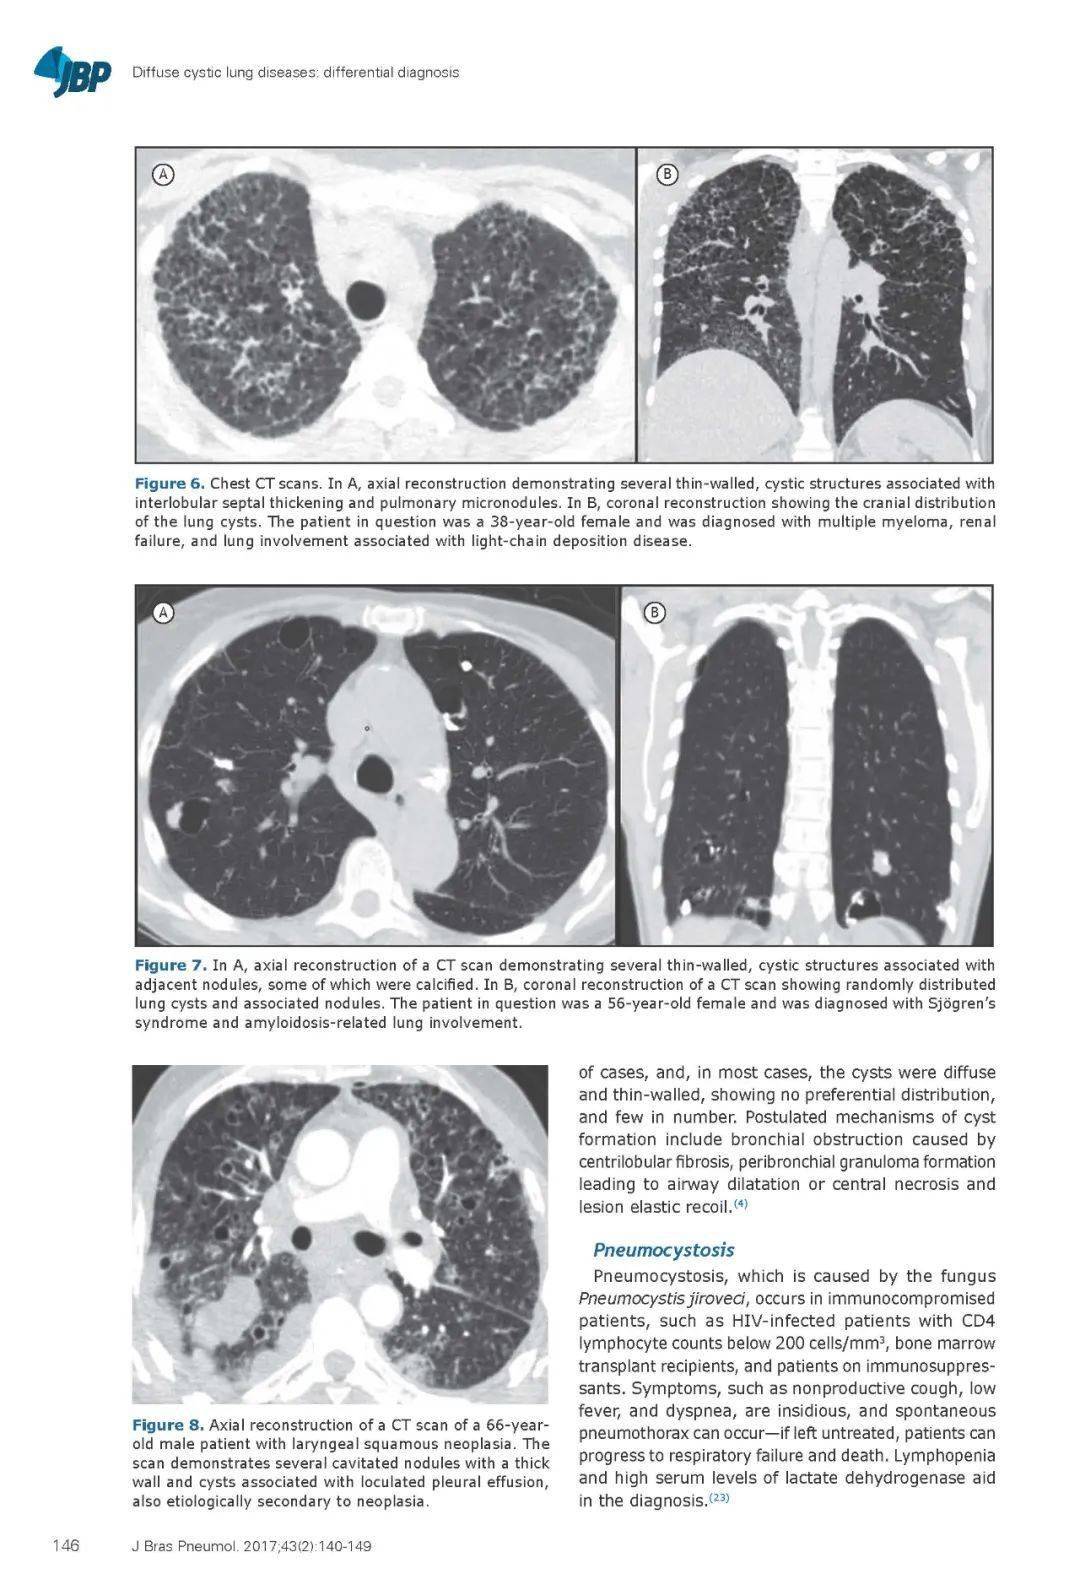

轻链由浆细胞分泌,沉积在肺泡壁、小气道和血管中。最常见的CT表现包括结节、淋巴结肿大和直径达2cm的弥漫性薄壁囊肿(图6)。认为囊肿是由于蛋白在管壁沉积导致的气道扩张(15)。

6 。患者为38岁女性,被诊断为多发性骨髓瘤、肾衰竭和轻链沉积性疾病相关的肺受累。胸部CT扫描轴位显示多发薄壁囊,伴有小叶间隔增厚和肺小结节。冠状面重建显示肺囊肿的解剖分布。

肺淀粉样变的CT表现包括结节、小叶间隔增厚、磨玻璃影和淋巴结肿大。肺囊肿是罕见的,最常被描述为局部淀粉样变与干燥综合征相关。囊肿形成可能机制包括炎性细胞导致气道变窄,从而形成一种活瓣结构,以及淀粉样沉积或淀粉样浸润血管造成缺血而破坏脆弱的肺泡壁。囊肿是薄壁的,主要分布于外周,常伴有结节或肿块(图7)。淀粉样变的诊断是通过刚果红染色组织学,刚果红染色在交叉偏振光下产生绿色的双折射。(16.17)

7 患者为56 岁女性,被诊断为干燥综合征和淀粉样变相关的肺受累。A CT 轴位显示几个薄壁、囊性结构,并伴有邻近结节,其中一些结节钙化。BCT 扫描的冠状面重建显示随机分布的肺囊肿和相关结节。